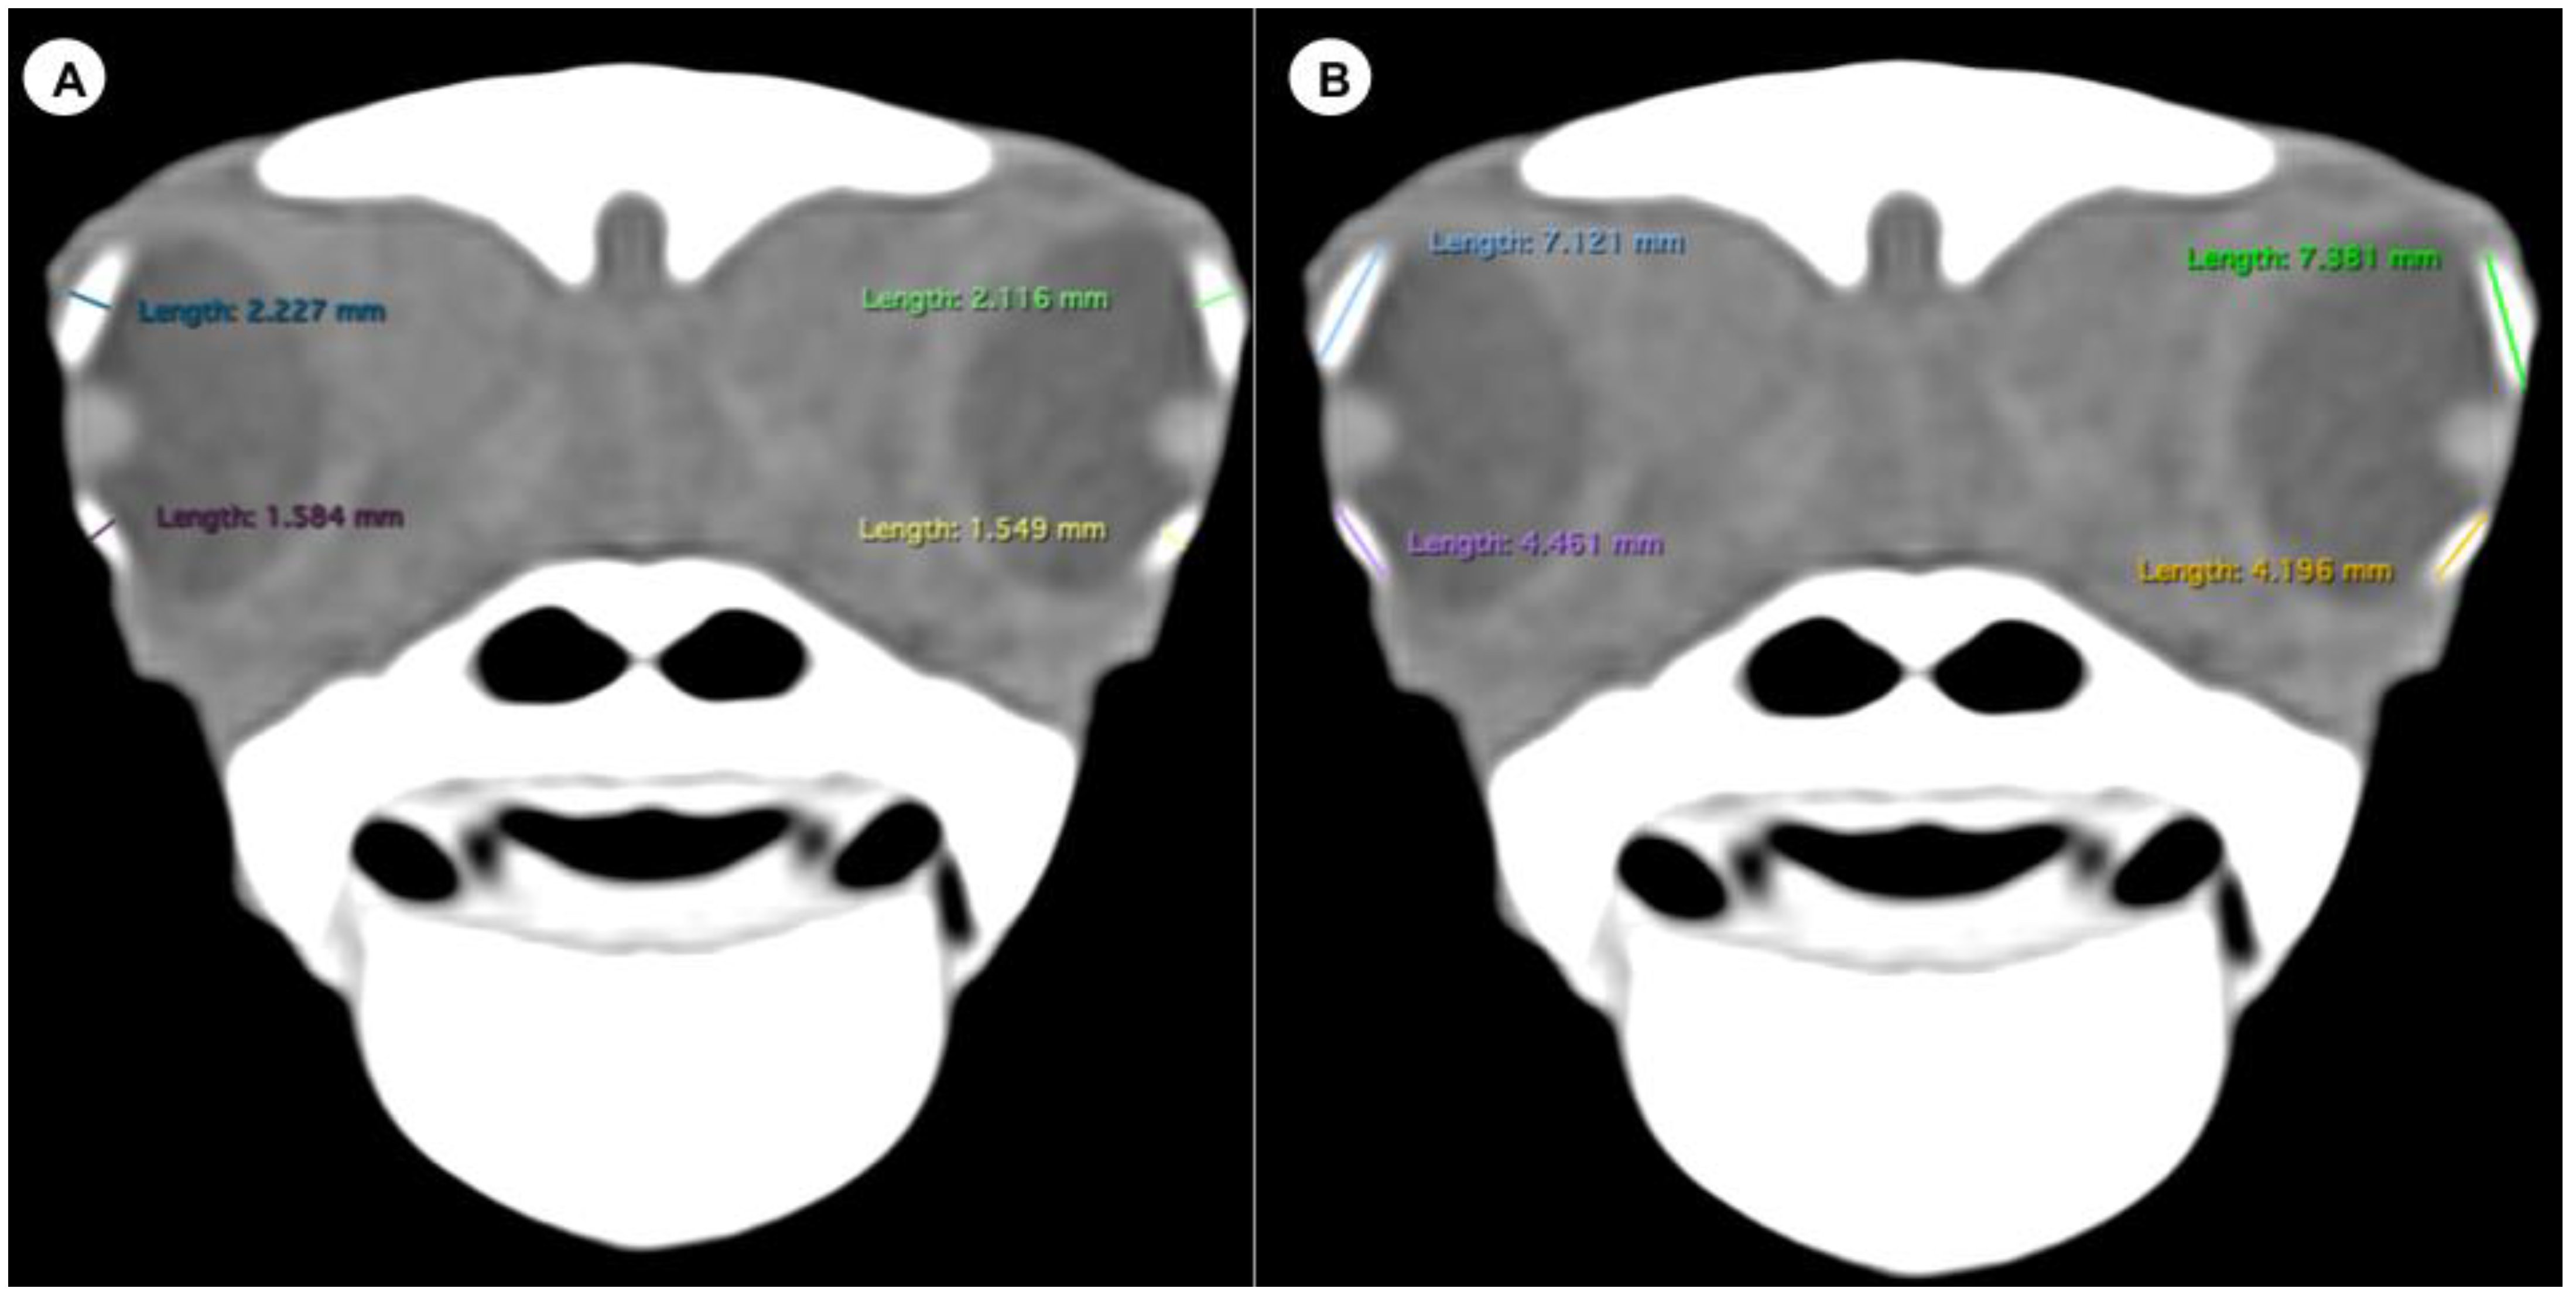

- Dorsal and ventral arch length: the thickness of the upper and lower regions of the scleral ring, with the corneal and scleral margins (Figure 2B).

Figure 2. Transverse CT image in soft tissue window of the C. caretta head with the width (A) and height (B) of the dorsal and ventral arches of the sclerotic ring. - -

- Width of the dorsal and ventral arches of the scleral ring, that is, of the upper and lower parts of the lateral portion of the ring (Figure 2A).

The means arch heights were 6.82 mm (range = 4.44–10.1) and 4.96 (range = 3.2–7.51) for the dorsal and ventral measurements, respectively. The difference between the dorsal and ventral arch height was statistically significant (p = 0.0006). At the same time, the means of the dorsal and ventral arch width were 2.81 mm (range = 1.89–6.71) and 2.57 mm (range = 1.8–5.56), respectively, with no significant differences.